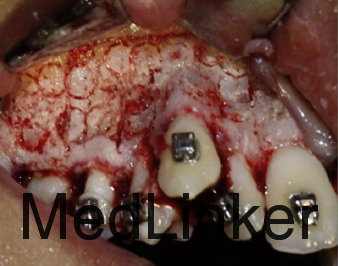

诊断:上牙弓严重横向不调。治疗:上颌颊侧骨皮质切开术+固定矫治+上颌腭侧固定扩弓。上颌上拖槽一周后行骨皮质切开术,如图,切开后全层翻瓣暴露骨皮质,于骨皮质上打孔,范围从牙槽骨顶端下方2mm到根尖下方2mm。根据牙槽厚度孔的深度从0.5mm到1.5mm不等,复位后间断缝合。同时腭侧粘接由带环,螺旋扩弓器制作的固定扩弓装置,即刻加力,转动完整的一圈。之后每周扩弓器打开1mm,连续8周,上颌牙弓被打开,扩弓器再维持2月,同时固定矫治器继续排齐整平。总疗程5个月2周。上颌宽度变化第一前磨牙间增加10mm,第二前磨牙间增加8.9mm,第一磨牙间增加8.3mm。但尖牙间宽度不变,这也是为什么扩弓后后期牙弓能够保持的原因,尖牙间宽度对维持牙弓稳定性非常重要。

3年后复诊,如图,仍然稳定。快扩和慢扩用于生长发育的患者,还是比较成功的,对于骨龄已经成熟的孩子,外科手术辅助的扩速腭部扩开可能是治疗的选择,本病例中的骨皮质切开术可以作为外科手术的替代方法,诱发颊侧的牵张成骨效应,促进表面骨质的沉积。相比于腭部切开手术,降低了风险。(该病例摘自Am J Orthod Dentofacial Orthop 2015;148:138-53 doi: 10.1016/j.ajodo.2014.08.023.)